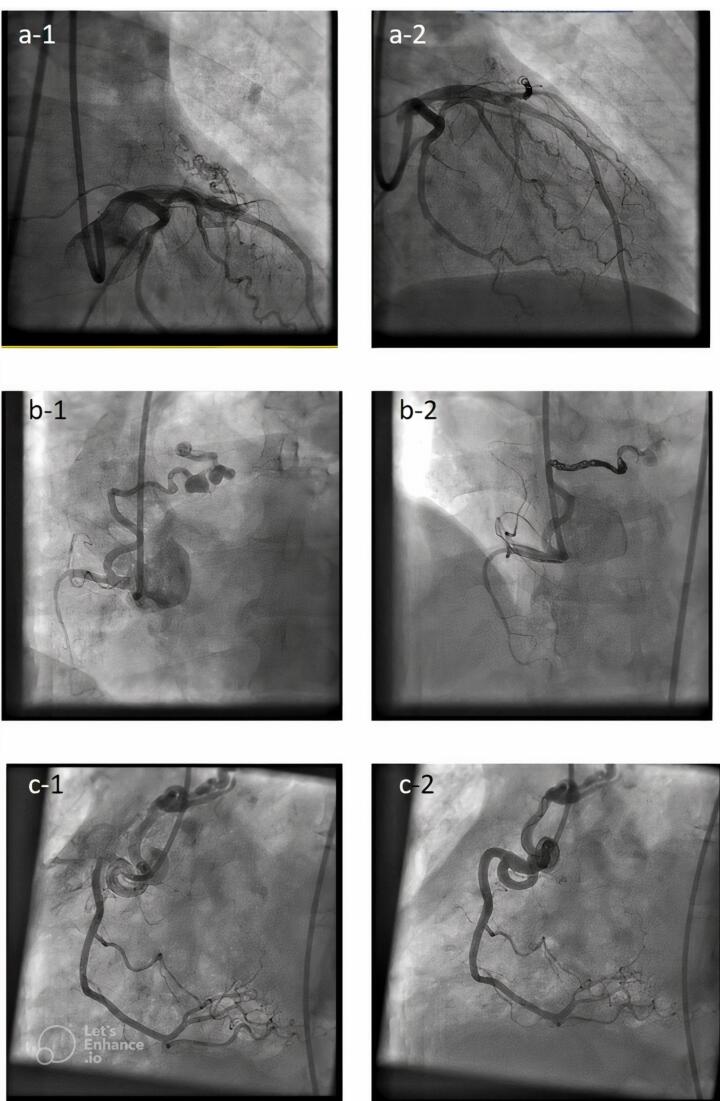

大多数先天性冠状动脉瘘(CAF)病例可自行缓解,有严重分流症状的患者需要手术干预。我们的目的是评估使用经导管介入方法治疗先天性冠状动脉瘘的成功率和结果。这项回顾性研究的对象是2015年至2020年间转诊至德黑兰拉贾伊心血管医疗研究中心的28例先天性冠状动脉瘘患者。通过评估医院记录收集了患者的基线特征,并每年对患者进行随访,以进行长期评估。28 名患者均通过经导管关闭了 CAF。其中 23 例为近端型(82.1%),5 例为远端型(17.9%)。11 名患者的瘘管来自 RCA(39.3%),11 名患者的瘘管来自 LAD 和对角线。最常见的引流部位是肺动脉(82.1%)。23 名患者使用了线圈(82.1%)。2 名患者使用了 PDA 闭塞器(7.1%)。一名患者使用了 VSD 闭塞器(3.6%),一名患者使用了 VSD+PDA 闭塞器组合(3.6%)。只有一名患者手术失败。有 4 名患者(14.3%)在手术后立即注射了不明显的残余分流物,但在随访期间分流物有所减少。在长期随访期间,没有一名患者出现明显的分流或临床症状。在并发症方面,只有一名患者发生了瘘管剥离。

Most cases of congenital coronary artery fistula (CAF) resolve spontaneously, symptomatic patients with severe shunting require surgical intervention. Our aim is to evaluate success rate and outcome of CAFs treatment using transcatheter interventional methods.This retrospective study conducted on 28 CAF patients who were referred to Rajaie Cardiovascular Medical and Research Center in Tehran between 2015 and 2020. Baseline characteristics were collected by assessing hospital records, and patients were followed up annually for long-term evaluation. All of 28 patients gone throughtranscatheter closure of CAF. In 23 patient's it was proximal type (82.1%) and in 5 patients was distal type (17.9%). In 11 patients, the fistula originated from the RCA (39.3%) and in 11 patients, it originated from the LAD and Diagonal. Most common drainage site was the pulmonary artery (82.1%). Coil used in 23 patients(82.1%). PDA occluder (7.1%) for 2 patients. VSD occluder for one patient (3.6%) and VSD+PDA occluder combination was used for one patient (3.6%). Procedure failure was in only one patient. Non-significant remaining shunt in the injection immediately after the procedure was seen in 4 patients (14.3%), which was reduced during the follow-up. None of the patients had significant shunt or clinical symptoms during long-term follow-up. As for complications, fistula dissection occurred in only one patient.The transcatheter interventional approach for the treatment of CAFs leads to favorable long-term results.